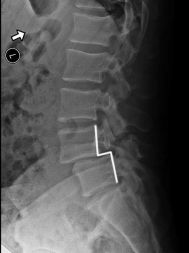

Spondylolisthesis is most commonly found in the lumbar spine as these levels bear the most weight. To assess instability, we take x-rays of a patient bending forward (flexion) and bending backwards (extension). Normally there would be no motion. The more motion seen between flexion and extension x-rays across an injured level, the greater the patient’s symptoms usually appear.

X-RAY SHOWING A PARS FRACTURE DEFECT

THE WHITE OUTLINE SHOWS THE SLIPPAGE.

When we look at the spine from the side, we can imagine a scotty dog. It is outlined above. The pars fracture is seen as a collar around the dog's neck. Instability and movement can cause the neck to widen. We will see this below in an X-ray example.